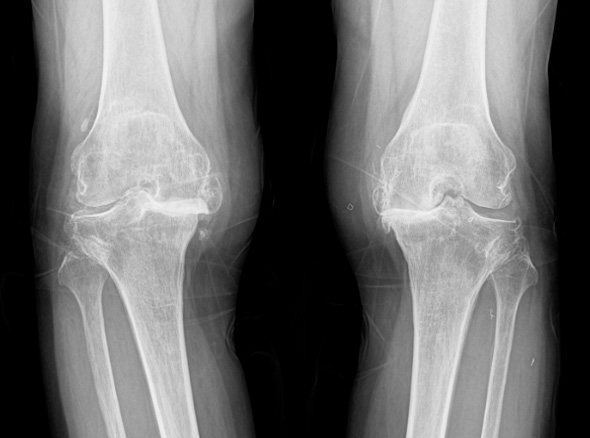

관절 마모 정도가 심하고 통증이 심한 환자분들은 재활치료나 약물만으로는 치료가 어려운 경우가 있습니다.

노화로 인해 연골이 닳아 통증,

운동 제한이 발생하는 경우

(계단 오르내리기, 구부리기, 쪼그려 앉기 등)

자가면역질환으로

관절 염증이 심한 경우

골절이나 심한 관절 손상으로

정상적인 기능이 어려운 경우

혈액 공급 장애로 인해

관절 조직이 괴사된 경우